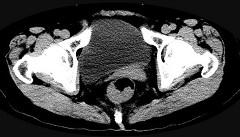

问题 男,56岁,排便形状改变,便不尽感,CT检查如图所示,下列说法正确的是 ( )

选项 A.肠壁上有蒂状新生物 B.其表面光滑,边界清楚 C.肠腔未见狭窄 D.此为直肠息肉 E.此为直肠癌

答案 E